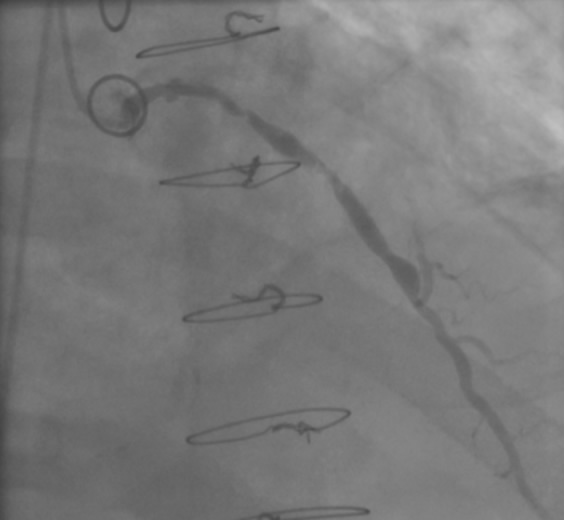

In the past, surgeons used rings to mark the ostia of the vein grafts substantially aiding the angiographer to localize the vein graft ostia during angiography. However, nowadays, it is not a usual practice. The lack of marker can increase the contrast use and radiation particularly in patients without the knowledge of the types and number of vein grafts. As mentioned earlier, right coronary grafts have usually a right sided take off from the aorta. Therefore, using standard view, left anterior oblique (LAO), which is used for right coronary artery catheterization is the view of choice. Left coronary bypass grafts have usually anterior take off. Therefore, a right anterior oblique (RAO) makes it easier to engage the left-sided vein graft ostia preventing foreshortening of the catheter tip. Using RAO, the catheter tip should be oriented to the right side of the screen. The vein grafts to the left system is based on the anatomical proximity of the native coronary to the aorta. Therefore, LAD graft ostia are usually closest grafts to the aortic valve followed by diagonal and circumflex grafts. Circumflex graft ostia usually have the highest take off from the aorta. There are occasional cases with different take off making vein graft angiography difficult. In such a situation, the angiography catheter has to be probed across the aorta in different level in order to engage the ostial vein graft. A non-selective strong contrast injection or aortogram may be necessary to delineate the unusual take off of missing vein grafts or documenting total occlusion of missing vein grafts. Total occluded vein grafts usually have a residual knob in the aorta that can be seen during angiography.

The most commonly used catheters for left heart catheterization and vein graft angiography can be seen in Figure 1 and Figure 4-13. Most of the vein grafts have horizontal take off and can be successfully engaged using a commonly used Judkins right number 4 (JR4) catheter. The JR4 catheter is the most commonly used catheter for the engagement of the right coronary ostium with horizontal take off. However, many vein grafts have unusual take off requiring different catheters. Many right coronary vein grafts have steep inferior take off making the ostial engagement with JR4 difficult or impossible (Figure 10). In such a scenario, a multipurpose catheter which has a shallow angulation is the best choice (Figure 11). The second major challenge in engaging vein graft ostia, particularly vein grafts supplying the left coronary arteries, is the shape of the aorta. A large aorta can make it very difficult for the JR4 catheter to reach the ostial vein grafts. In such a situation, Amplatz (AR) right and left (AL) catheters can be very helpful to reach the vein graft ostia. Amplatz catheters have a larger primary curve and have been used successfully in unusual superior take off of left coronary arteries or vein grafts and in large aorta. Amplatz catheters are available in different sizes (from smaller to larger curve: AR 1, AR2, AL2, AL2 and AL3). Occasionally, a very superior take off of a vein graft requires specially designed bypass graft catheters. Amplatz catheters are also extremely helpful in engaging native right coronary ostium with anterior take off.

PCI of the vein and arterial grafts have unique challenges. For any PCI, guide support is very important for successful balloon and stent delivery. In a tortuous vein graft with a steep angle, advancement of a stent can be very difficult and challenging. Therefore, it is important to choose the best available catheter before starting PCI. Similar to the right coronary angiography, a JR4 guide catheter is most commonly used in this setting. However, Amplatz guide catheters for left vein grafts and multipurpose catheters for right vein grafts are better choices in certain anatomy. In Figure 8 and Figure 10 two examples of poor guide support in two vein graft interventions can be seen. Initially, a JR4 guide was used for PCI of the vein graft supplying the left anterior descending artery (LAD) without any success. However, after changing the guide to an Amplatz left 2 guide catheter, we achieved excellent support without any difficulty in advancing two stents (Figure 9). In Figure 10, difficulty is illustrated in engaging the vein graft ostium supplying the right coronary artery with a JR4 catheter. This vein graft has a very steep inferior take off from the aorta. After changing the guide to a multipurpose catheter, we were able to deliver three stents successfully without any difficulties (Figure 11). Similar challenges exist in the treatment of the left IMA or right IMA. These arterial grafts can be extremely tortuous making stent delivery very difficult. It may be necessary to use short length stents for a better deliverability or stents with lowest profile. Usually, similar to the native coronary intervention, a 6 French guide is appropriate for the routine use.